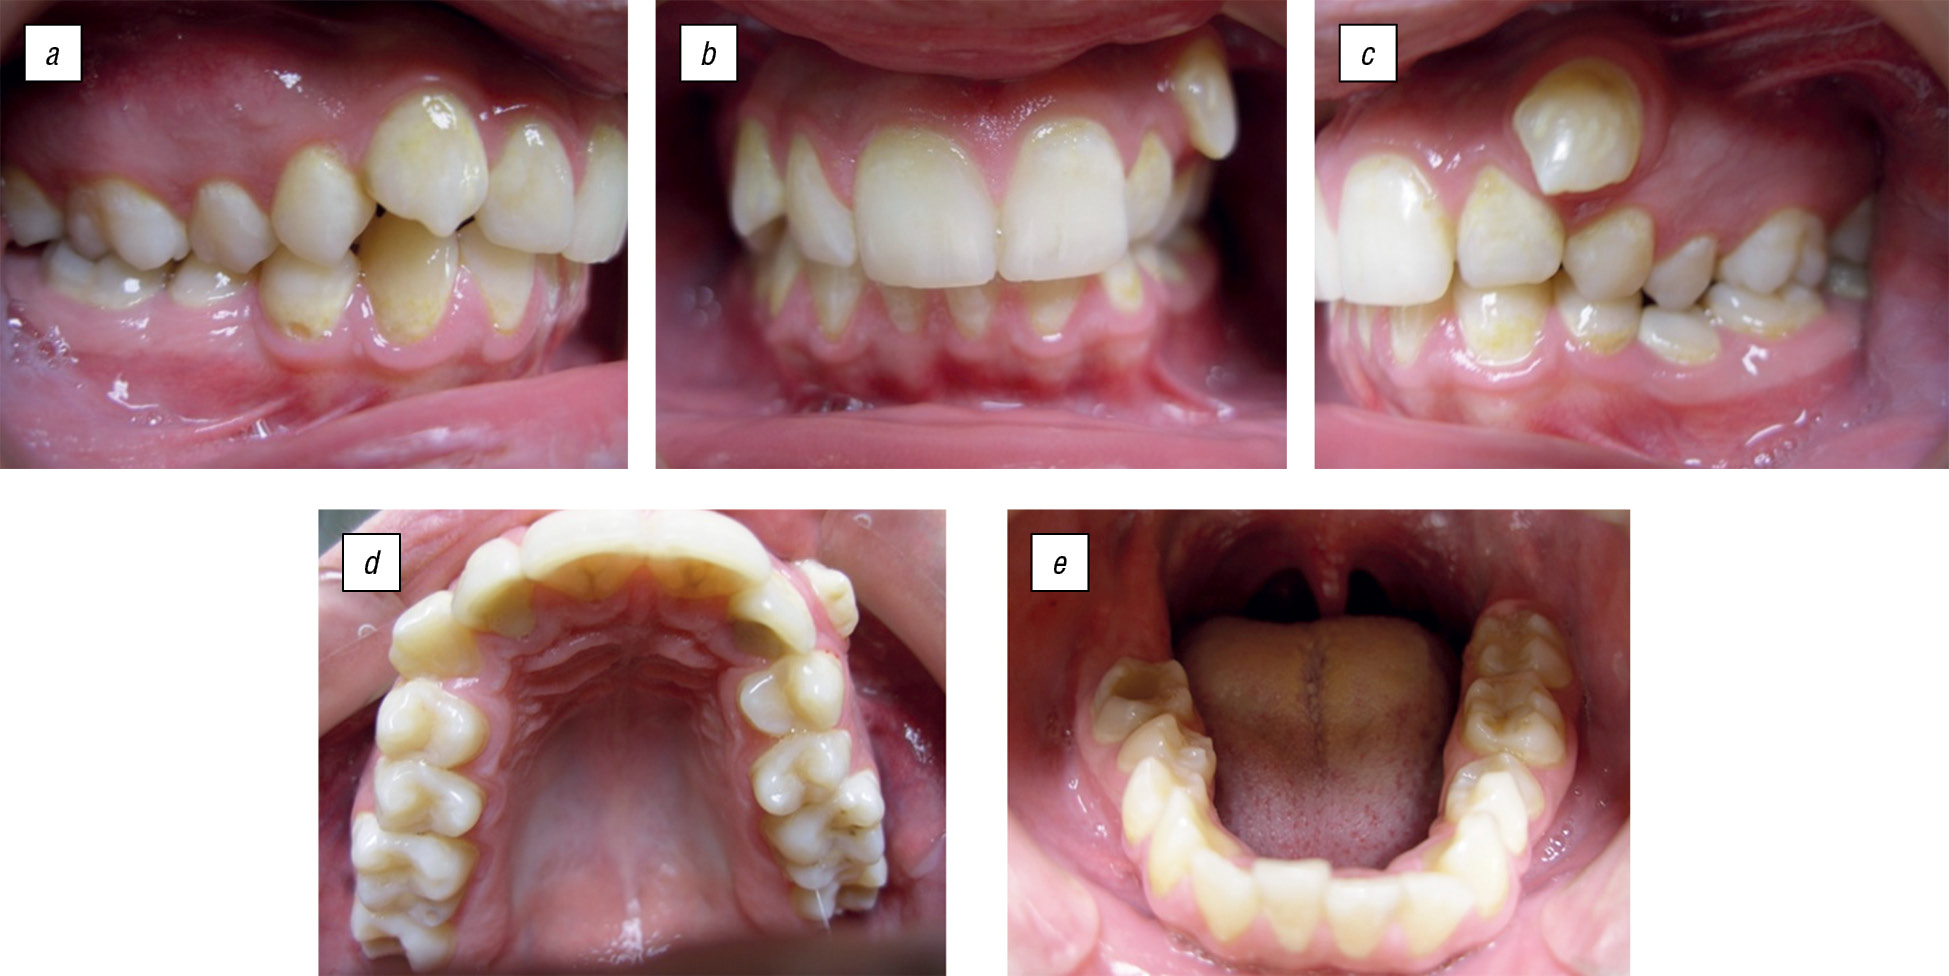

Соотношение зубных рядов по II классу Энгля (дистальная окклюзия) (рис. 2).

Рис. 2. Смыкание зубов-антагонистов пациента П., 15 лет: а — справа; b — передних; с — слева. Зубные ряды верхней челюсти (d); нижней челюсти (e) / Fig. 2. Occlusion of antagonistic teeth of patient P., 15 years old: a — right; b — front; c — left. Dentition upper jaw (d); lower jaw (e)

Результаты проведенного клинического обследования позволяют сделать вывод о наличии у пациента зубочелюстно-лицевой аномалии. На ортопантомограмме пациента выявлено наличие 32 постоянных зубов, зубы 1.8, 2.8, 3.8, 4.7, 4.8 находятся в ретенции (рис. 3). Для уточнения проведена ТРГ головы пациента в боковой проекции. Анализ ТРГ в боковой проекции в программе Dolphin Imaging (рис. 4) позволил поставить предварительный диагноз — дистальная окклюзия, гнатическая форма.